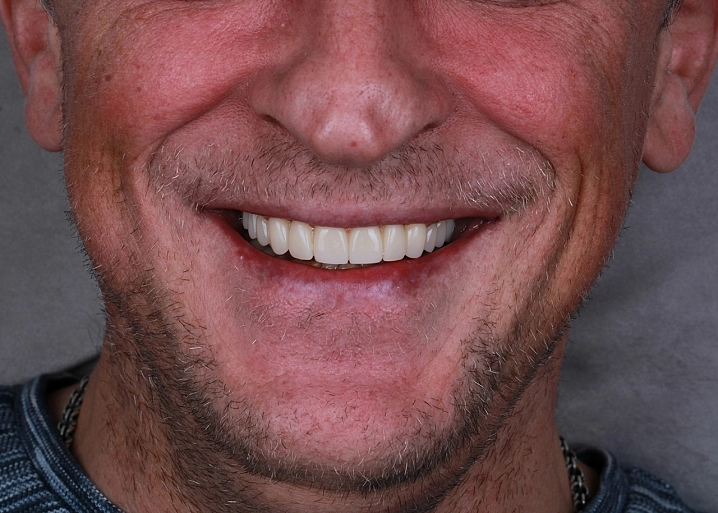

Циркониевый мостовидный протез представляет собой постоянную конструкцию, которая фиксируется на несколько опорных имплантов. Протез устанавливается после периода остеоинтеграции имплантатов через 3-6 месяцев. Коронки соединены между собой каркасом и представляют единое целое.

Существует 2 вида реставраций: с нанесением керамической массой и методом раскрашивания. Второй вариант в нашей клинике применяется чаще всего. Этот метод дает высокий эстетический результат. Первый вариант с нанесением керамики имеет недостаток, керамика может со временем скалываться, что вызывает неудобство в использовании протеза.